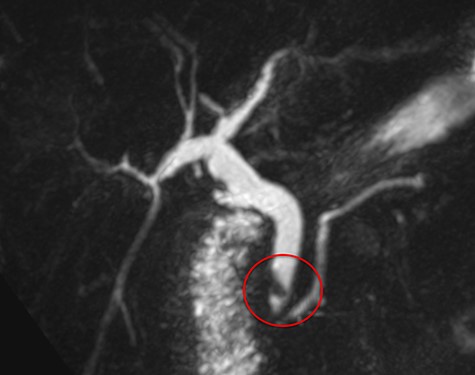

A 71-year-old woman with a history of LC for acute cholecystitis 6 years earlier was admitted with right upper quadrant abdominal pain, jaundice and fever. On admission, her vital signs were body temperature 38.2°C, pulse rate 96/min, respiration rate 21/min, blood pressure 100/60 mmHg and SpO2 98%. Her laboratory tests showed leukocytosis (19.200/ml), an erythrocyte sedimentation rate of 25 mm/h, C-reactive protein of 26 mg/l and altered liver function tests with cholestatic pattern: total bilirubin 4.95 mg/dl (normal up to 1.2), direct bilirubin 4.18 mg/dl, alkaline phosphatase 1083 IU/l (normal up to 150), gamma-glutamyl transferase 169 IU/l (normal up to 45), aspartate transaminase 281 IU/l (normal up to 40) and alanine transaminase 330 IU/l (normal up to 41). Serum amylase and lipase were normal. Abdominal ultrasound showed biliary tract dilatation but not obstructive cause, with a maximum diameter of the CBD of 17.6 mm. A subsequent magnetic resonance cholangiopancreatography (MRCP) found a filling defect in the distal CBD (Fig. 1). ERCP extraction was attempted, but it was impossible to progress the catheter due to an irregular distal bile duct stenosis. An abdominal computed tomography (CT) scan was therefore performed and showed a foreign body with radiopaque characteristics in the distal CBD consistent with a metallic clip (Fig. 2). Given that the object could not be removed by ERCP due to technical difficulties in biliary cannulation, laparoscopic bile duct exploration was decided.

Abdominal CT scan. A metallic artifact is observed in the distal common bile duct (red circle) in axial (A) and coronal (B) planes.